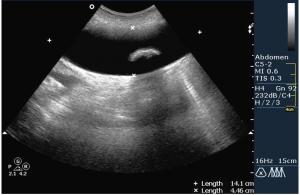

По всей видимости пузырь увеличен, напряжен, содержимое 2 крупных конкремента,один из которых вклинен.

Доктор Марио! Фиксированный камень шейки желчного пузыря. Еще один камень в просвете. Не знаю, употребляете ли Вы такой термин, но я бы еще сказал "водянка желчного пузыря". Показание к оперативному лечению желче-каменной болезни. Симптома "трехслойности стенки" не увидим. Пузырь перерастянут. Кстати, в последнее время встречается все большее и большее количество случаев желче-каменной болезни у пациентов молодого возраста. От 18 лет.

Вы совершенно правы, это холецистолитиаз с вклинённым камнем шейки (impacted GB neck stone) с перерастяжением пузыря, или водянка (GB Hydrops). Сегодня была успешнo оперирована.